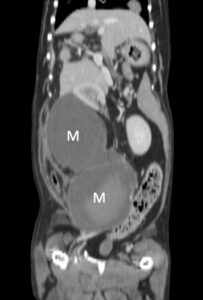

- 原発腫瘍が極めて小さくても巨大な転移リンパ節を形成しうる(図1)

(図1)右肛門嚢に小豆大の腫瘤を認めた症例の腹部CTコロナル像。巨大なリンパ節転移巣(M)が認められる